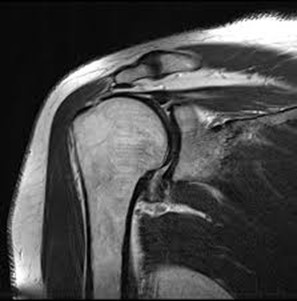

• conditions involving musculoskeletal system including the knee, shoulder, ankle, wrist and elbow as well as ligament, meniscus and rotator cuff tears

• injuries, tumors, and degenerative disorders of bone joints, spine, ligaments, meniscus in the skeletal muscular structure of the body